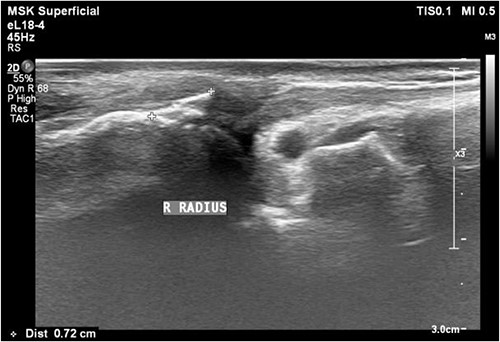

A 61-year-old male who denied any systemic disease, with a past medical history of a left distal radial fracture, which was treated with ORIF with a plate on 29 January 2017. He presented to the plastic surgery Outpatient Department (OPD) in July 2020 with a protruding mass over his left palmar wrist, which had been causing him pain for the past 3 weeks. On examination, poor flexion of the left thumb was noted. Upon suspicion of a ruptured FPL tendon, a sonogram was arranged, which confirmed the diagnosis (Fig. 1). After discussion with the patient, it was decided that he would undergo surgery.

Sonogram of the left wrist showing a ruptured FPL tendon. The arrow points to the discontinuity in the tendon, indicating the site of rupture.